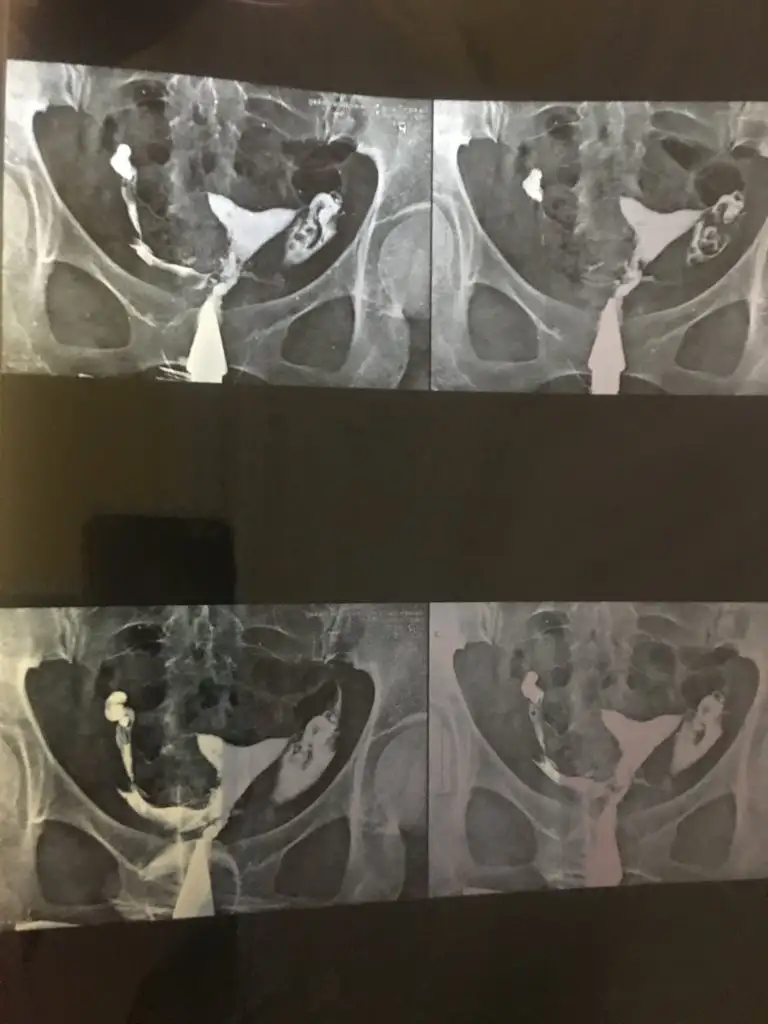

Benim rahim filmim bu şekilde raporda hidrosalpink yazmıyor ama doktorum tek tüpümde sıvı birikmiş dedi bilen arkadaşlar yorumlayabilir mi lütfen ?

Eklentiler

• 67D094B1-DDB2-4E64-AD06-713F5FADE428.webp

67D094B1-DDB2-4E64-AD06-713F5FADE428.webp

24,3 KB · Görüntüleme: 51